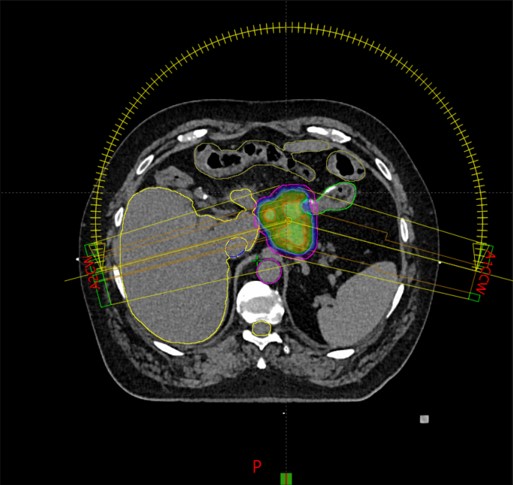

SBRT meta lymphonodi hepatogastrici (7/2020)

Rezultat – 52 mjeseca nakon RK

Potpuna metabolička regresija tretiranog patološkog limfnog čvora